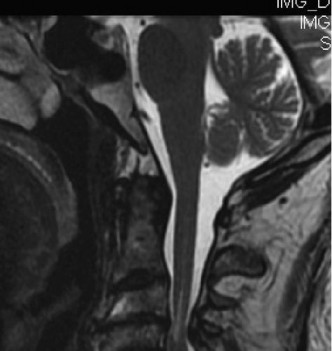

CASE 1 A 63-year-old male sustained a hyperextension injury to his neck while diving into a pool. Upon presentation, he reports decreased sensation in his hands and decreased strength in his arms and wrists, but no lower extremity complaints. On motor examination, he has 5/5 strength in his deltoids and elbow flexors and 4/5 strength in the elbow extensors, wrist extensors, and finger flexors. Lower extremity motor examination is normal. Sensation is decreased to light touch in both hands. Otherwise his sensation is preserved. Images of his cervical spine are shown in Figures 1–1 to 1–3.

Figure 1–2

The correct answer is (B). The clinical scenario describes a patient with central cord syndrome (CCS). CCS continues to be the most common incomplete spinal cord injury accounting for 15.7% to 25% of all spinal cord injuries. The characteristic presentation is an extension moment injury in a previously spondylotic and stenotic spine. Figures 1–1 to 1–3 demonstrate a spondylotic spine with central narrowing and CSF effacement that is worst at the C3–4 level. Bleeding, edema, and/or Wallerian degeneration lead to damage of the lateral corticospinal tract which is the main descending motor tract in the spinal cord. The more central anatomic position of the homunculus to the upper extremities places them at greater risk than those to the lower extremities. As such, injury to the lateral corticospinal tract is characterized by upper more than lower extremity involvement and motor deficits being more pronounced than sensory deficits.